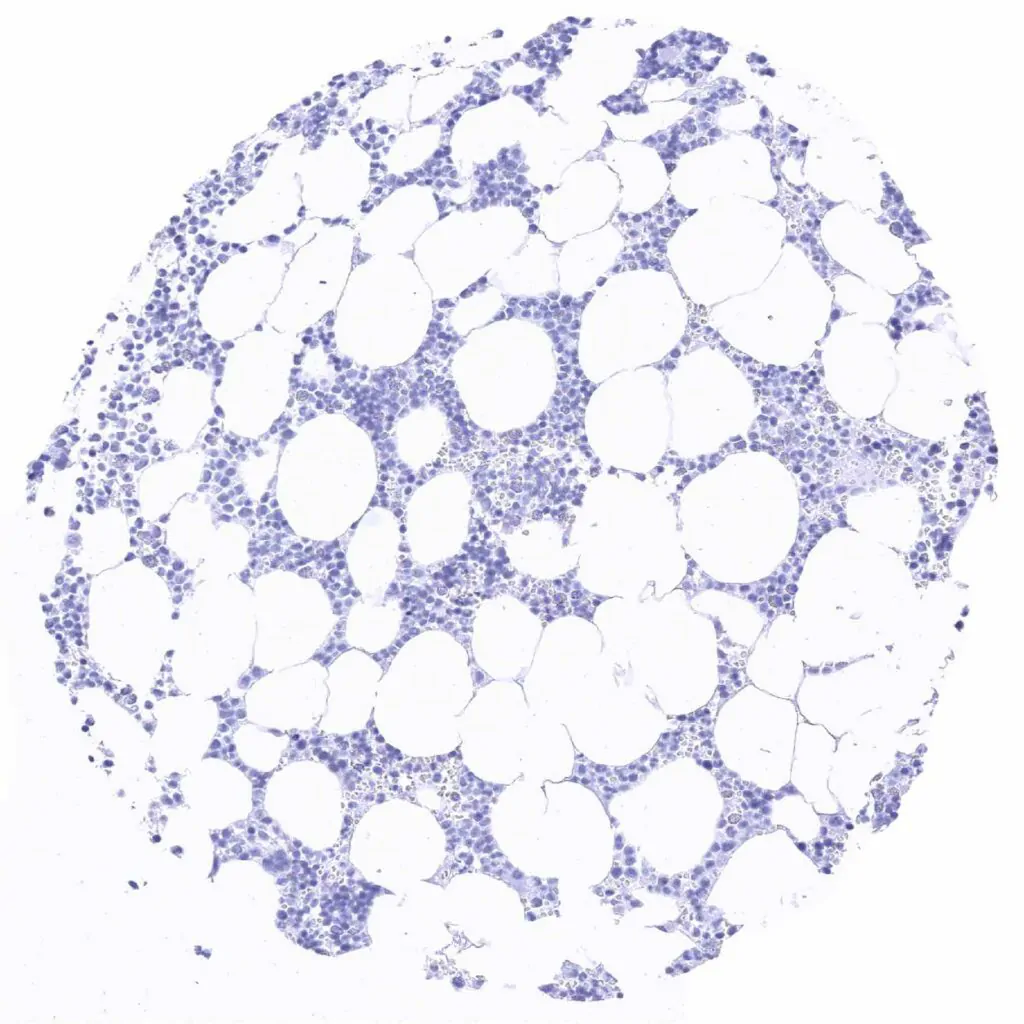

Bone marrow